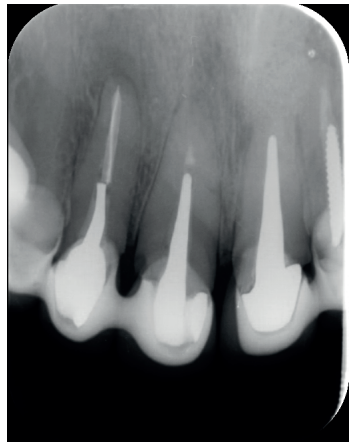

El paciente aporta como estudio radiológico una ortopantomografía (OPG), (Figura 1). Se realizaron radiografías periapicales (Figuras 2 y 3), así como exploración clínica incluyendo la valoración periodontal de los dientes afectados, sin observar profundidades de sondaje aumentadas que pudieran indicar la existencia de lesiones endoperiodontales.

A los seis meses el paciente acudió a revisión sin ninguna sintomatología, tanto a nivel anterior como posterior. En las radiografías periapicales se apreció una disminución en el tamaño de las lesiones periapicales radiolúcidas preexistentes (Figuras 10 y 11). Dado que faltaba tratar la lesión del 25, se realizó CBCT de control donde se comprobó la mejoría a nivel del 26 (Figura 12), por lo que se programó la microcirugía del 25.

Una vez realizada la microcirugía del 25, el paciente no volvió a presentar ninguna sintomatología y las tomografías de control a 12 meses (en 25) y a 18 meses en los dientes restantes mostraron la regeneración de las lesiones periapicales radiolúcidas preexistentes en todos los dientes tratados (Figuras 13 a 16).